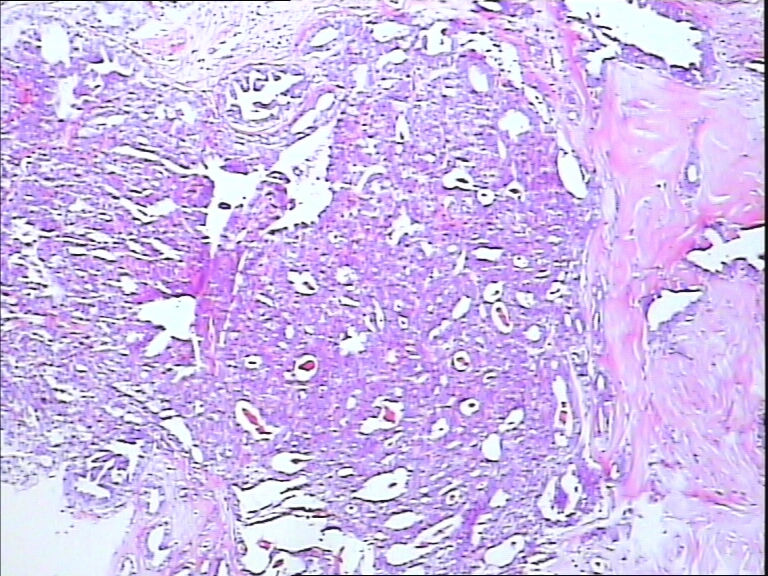

B3785左乳头包块!

42y

左乳头有3mm结节

灰白不整形组织一块:0.7*0.5*0.4

• 左乳头包块!图1

图1

标签:导管内乳头状肿瘤

导管内乳头状瘤

乳头腺瘤(nipple duct adenoma)或称乳头的乳头状瘤

导管内乳头状结构,细胞无异型性,诊断导管内乳头状瘤。